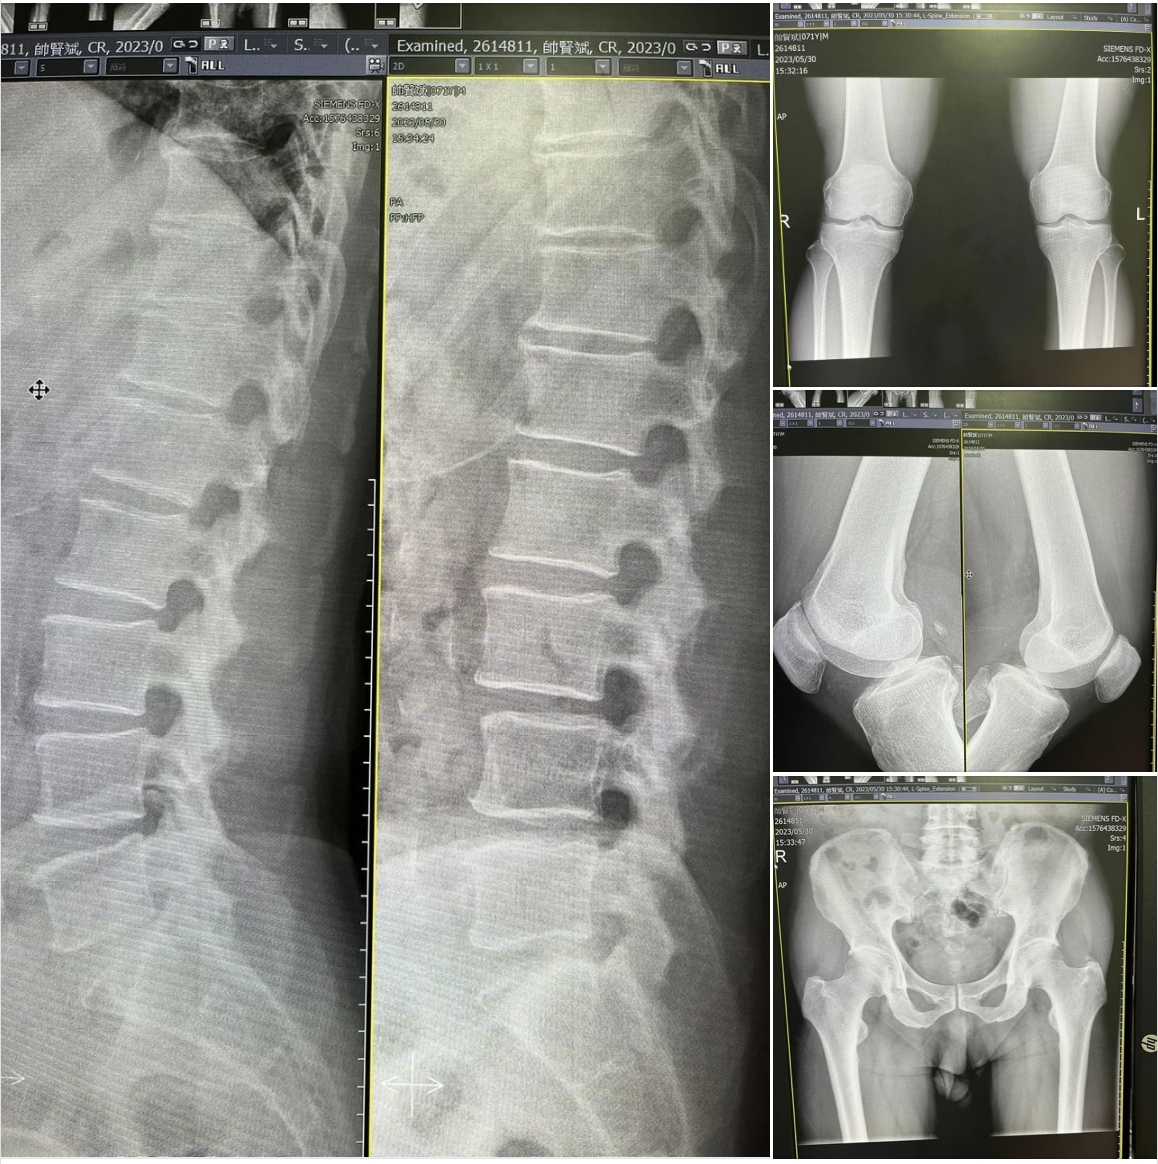

「聽到我在爬山,也有身旁的朋友在問年紀大的人到底適不適合登山?登山是不是會對膝蓋產生長期的負面影響?」不只是帥賢斌身邊友人的疑惑,這也是許多人對於登山運動的懷疑。對六十歲才開始接觸登山的帥賢斌來說,他認為這或許這並非絕對,應有還有探索答案的空間。不同於醫界的主流論調,帥賢斌認為正確的用力方式與訓練,爬山可以是對膝蓋有益的。對這項主張的探索,帥賢斌也已持續近十年。

過往關於膝蓋的研究,一般會歸類在骨科或復健科,讓人不禁好奇的是,以婦產跟麻醉為專業的帥賢斌,在並非本身領域的議題,是否會有失準之處?「登山會不會傷膝蓋,不是危及生命的問題,也不是一種疾病,所以相關的研究不多。但對我、對想要爬山的人很重要。面對一個尚未明朗的主題,我想醫療分工細化固然重要,但作為醫師應該保持更開放的眼界,看到問題的本質。」

近期,帥賢斌也計劃將自己累積近十年的觀察投稿至醫學刊物,也期待進一步深入研究。他同時將相關內容集結為第六本書《銀髮飛揚 膝行萬里》,預計於 2023 年 8 月出版。